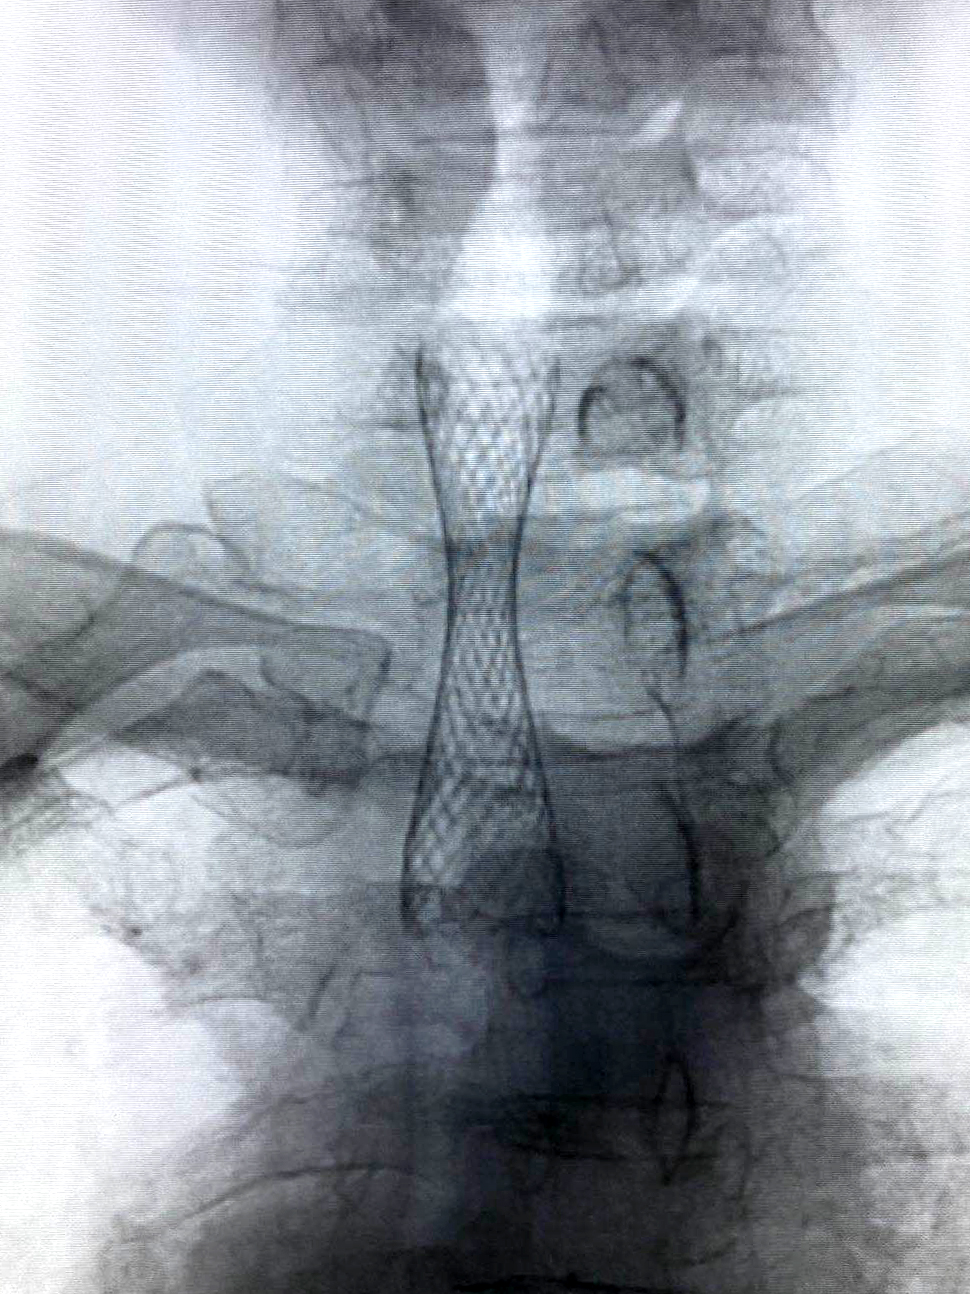

但這些問題統(tǒng)統(tǒng)難不倒我們經(jīng)驗豐富、身經(jīng)百戰(zhàn)的放射科介入團隊。局麻下,他們通過導(dǎo)管將導(dǎo)絲順利插入氣管,再順沿導(dǎo)絲置入氣管支架套裝,準(zhǔn)確定位后快速釋放支架,全程僅用時3分鐘。支架完全打開,將只有一線生機的氣管牢牢撐開,吹風(fēng)樣的呼吸聲完全消失,患者瞬間恢復(fù)正常呼吸,效果立竿見影。